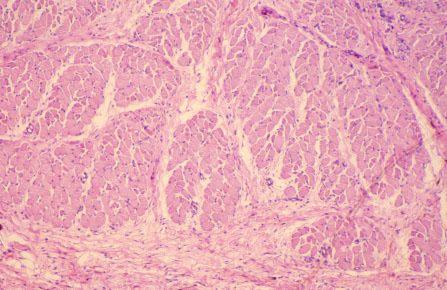

VIII-11, Slide 63, Rectoanal Junction (H&E). This is a cross-section of skeletal muscle of the external anal sphincter. Loose connective tissue is present at the bottom of the image.